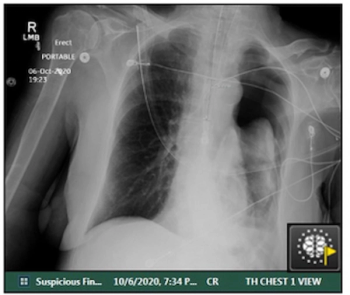

For clinically actionable pneumothorax, an artificial intelligence algorithm demonstrated a 93 percent AUC and a 96 percent specificity rate in a study involving chest X-rays from over 27,000 adults.